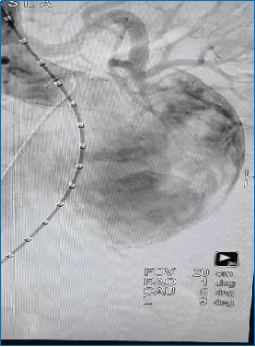

腹主动脉造影示:似“胃”样的腹主动脉瘤

经过几天的术前充分准备,7月19日李林锋团队给患者行局麻下腹主动脉瘤腔内隔绝术,手术仅仅花了一个小时。术后患者返回病房整个状态比之前有明显好转,李林锋、余龙辉、涂伟玲等医生术后查房时,大叔说:“这个介入手术真是神奇,不用开刀就解决了我的大问题,不瞒大家说,我真的很害怕手术,有了上次的开胸手术经历,我想到就是颤抖的……真是感谢您们的辛苦付出和高超的技艺!”余龙辉医生回答说:“微创介入手术创伤小,恢复快,可以明显减轻痛苦,但还是需要商讨一个合适的方案来彻底解决隐患。”